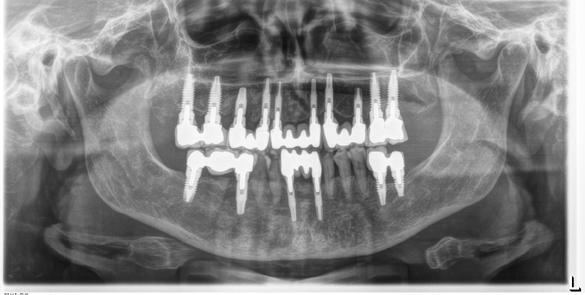

Figura 1. Radiografía inicial de la paciente. Se observa edentulismo total superior, a excepción del molar del primer cuadrante, indicado para exodoncia. En la mandíbula se aprecia pérdida ósea horizontal generalizada secundaria a la evolución de la enfermedad periodontal.

En la radiografía inicial (Figura 1) se observa la pieza 17 con pérdida ósea significativa, así como una reabsorción ósea homogénea a lo largo de todo el arco superior. En la arcada inferior se aprecia pérdida ósea horizontal generalizada y defectos localizados, como una lesión en cuña en la pieza 46. Ante esta situación, se decide realizar la exodoncia del molar remanente del

El mantenimiento periodontal y la implicación de la paciente en las medidas de autocuidado se mantuvieron de forma constante durante 23 años (Figura 25). La ortopantomografía realizada en una de las visitas de control mostró estabilidad completa de los implantes, sin signos radiográficos de pérdida ósea patológica.